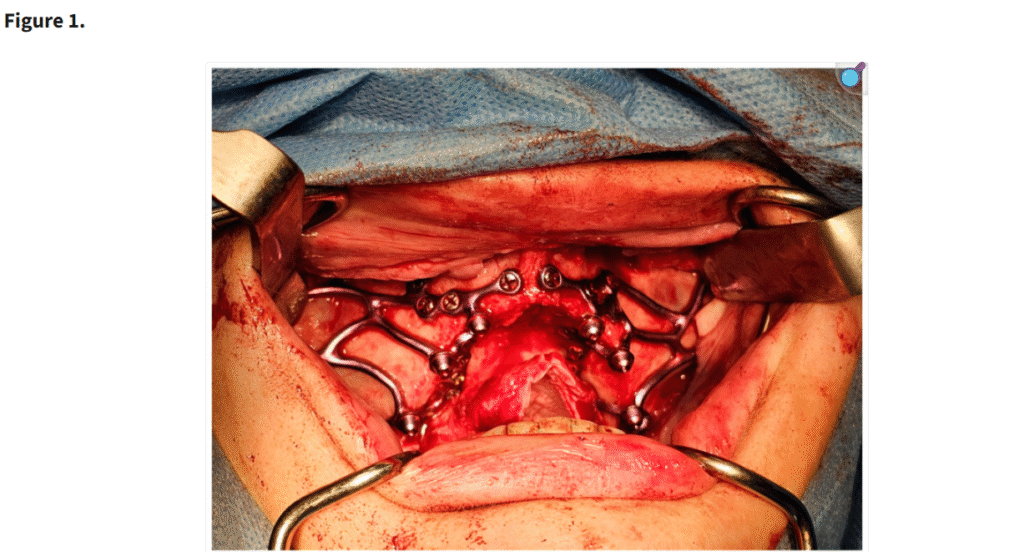

十分な視野が得られた段階で、患者の上顎解剖に正確に適合するように設計されたカスタムサブ骨膜下インプラントを歯槽堤上に配置した(Figure 1)。一部の症例では、歯槽堤が狭く高い場合にテンプレートを用いて骨を削除した(Figure 2・Figure 3)。手術中に頬脂肪体が脱出した場合には、MaIインプラント®(Integra Implants®, ロッジ、ポーランド)の前庭側表面に縫合した(Figure 4)。また一部の症例では、オトガイ部や外斜線から骨片を採取し、MaIインプラントの枝を覆う目的で使用した(Figure 5)。

「セルフタッピングスクリューで固定された MaI インプラント®(Integra Implants®, ロッツ〔ポーランド〕)の埋入。写真は、自家骨片でインプラントを被覆する前に撮影されたものである。」